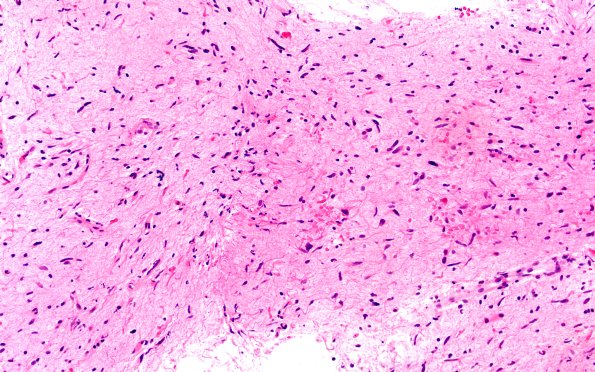

High-Grade Astrocytoma with Piloid features (HGAP)

2B3-6 Other areas are hypocellular with piloid cells H&E)